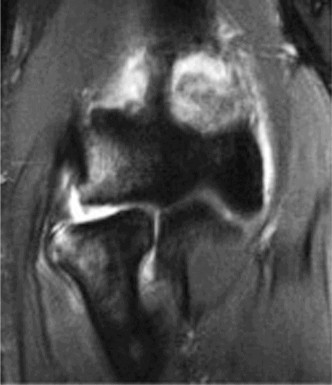

The correct answer is (B). An MRI showing a rotator cuff tear is considered diagnostic of a rotator cuff tear because of its high sensitivity, specificity, and accuracy. It has superb soft tissue imaging abilities (see Fig. 2–5). However, it should be noted that while MRI usually can differentiate between partial- and full-thickness rotator cuff tears, this varies with the power and accuracy of the MRI facility. This is also true with the ability of MRI to differentiate between partial-thickness rotator cuff tears and subacromial bursitis. An arthroscopy is needed for definitive differentiation of these pathologies.

Figure 2–5_Coronal oblique view MRI slice of a left shoulder. (Reproduced with permission from Smithius R and van de Woude HJ. Shoulder MR Anatomy: Normal Anatomy, Variants, and Checklist. _Radiology Assistant. April 2, 2012.)

Shoulder CT scans (Answer A) are not typically used to diagnose rotator cuff tears. X-rays, aka roentgenograms (Answer C), can show signs of rotator cuff pathology but are not diagnostic. Some signs of chronic rotator cuff tears that are sometimes seen on AP view x-rays include calcific tendonitis, calcification of the coracohumeral ligament, proximal migration of the humerus, and cystic changes of the greater tuberosity. An outlet view x-ray can show a type III (hooked) acromion, which is correlated with a higher rate of rotator cuff tears, or an OS acromiale, which would require special consideration for surgical treatment. Shoulder arthrograms (Answer D) are used primarily only when MRI is contraindicated and are considered positive for a rotator cuff tear if dye leaks from the glenohumeral joint into the subacromial space. MR arthrogram (Answer E) has been shown to have equivalent diagnostic ability compared with standard MRI and can be used to diagnose rotator cuff tears. However, it adds an additional step and cost to a standard MRI, and it does not offer any additional diagnostic benefit for rotator cuff pathology. Therefore, standard MRI is preferred to MR arthrogram.

Shoulder ultrasound is another modality that can be used to diagnose rotator cuff tears. It is generally less expensive than MRI but the sensitivity and specificity are more operator-dependent. Objectives: Did you learn...? Clinically diagnose a rotator cuff tear?